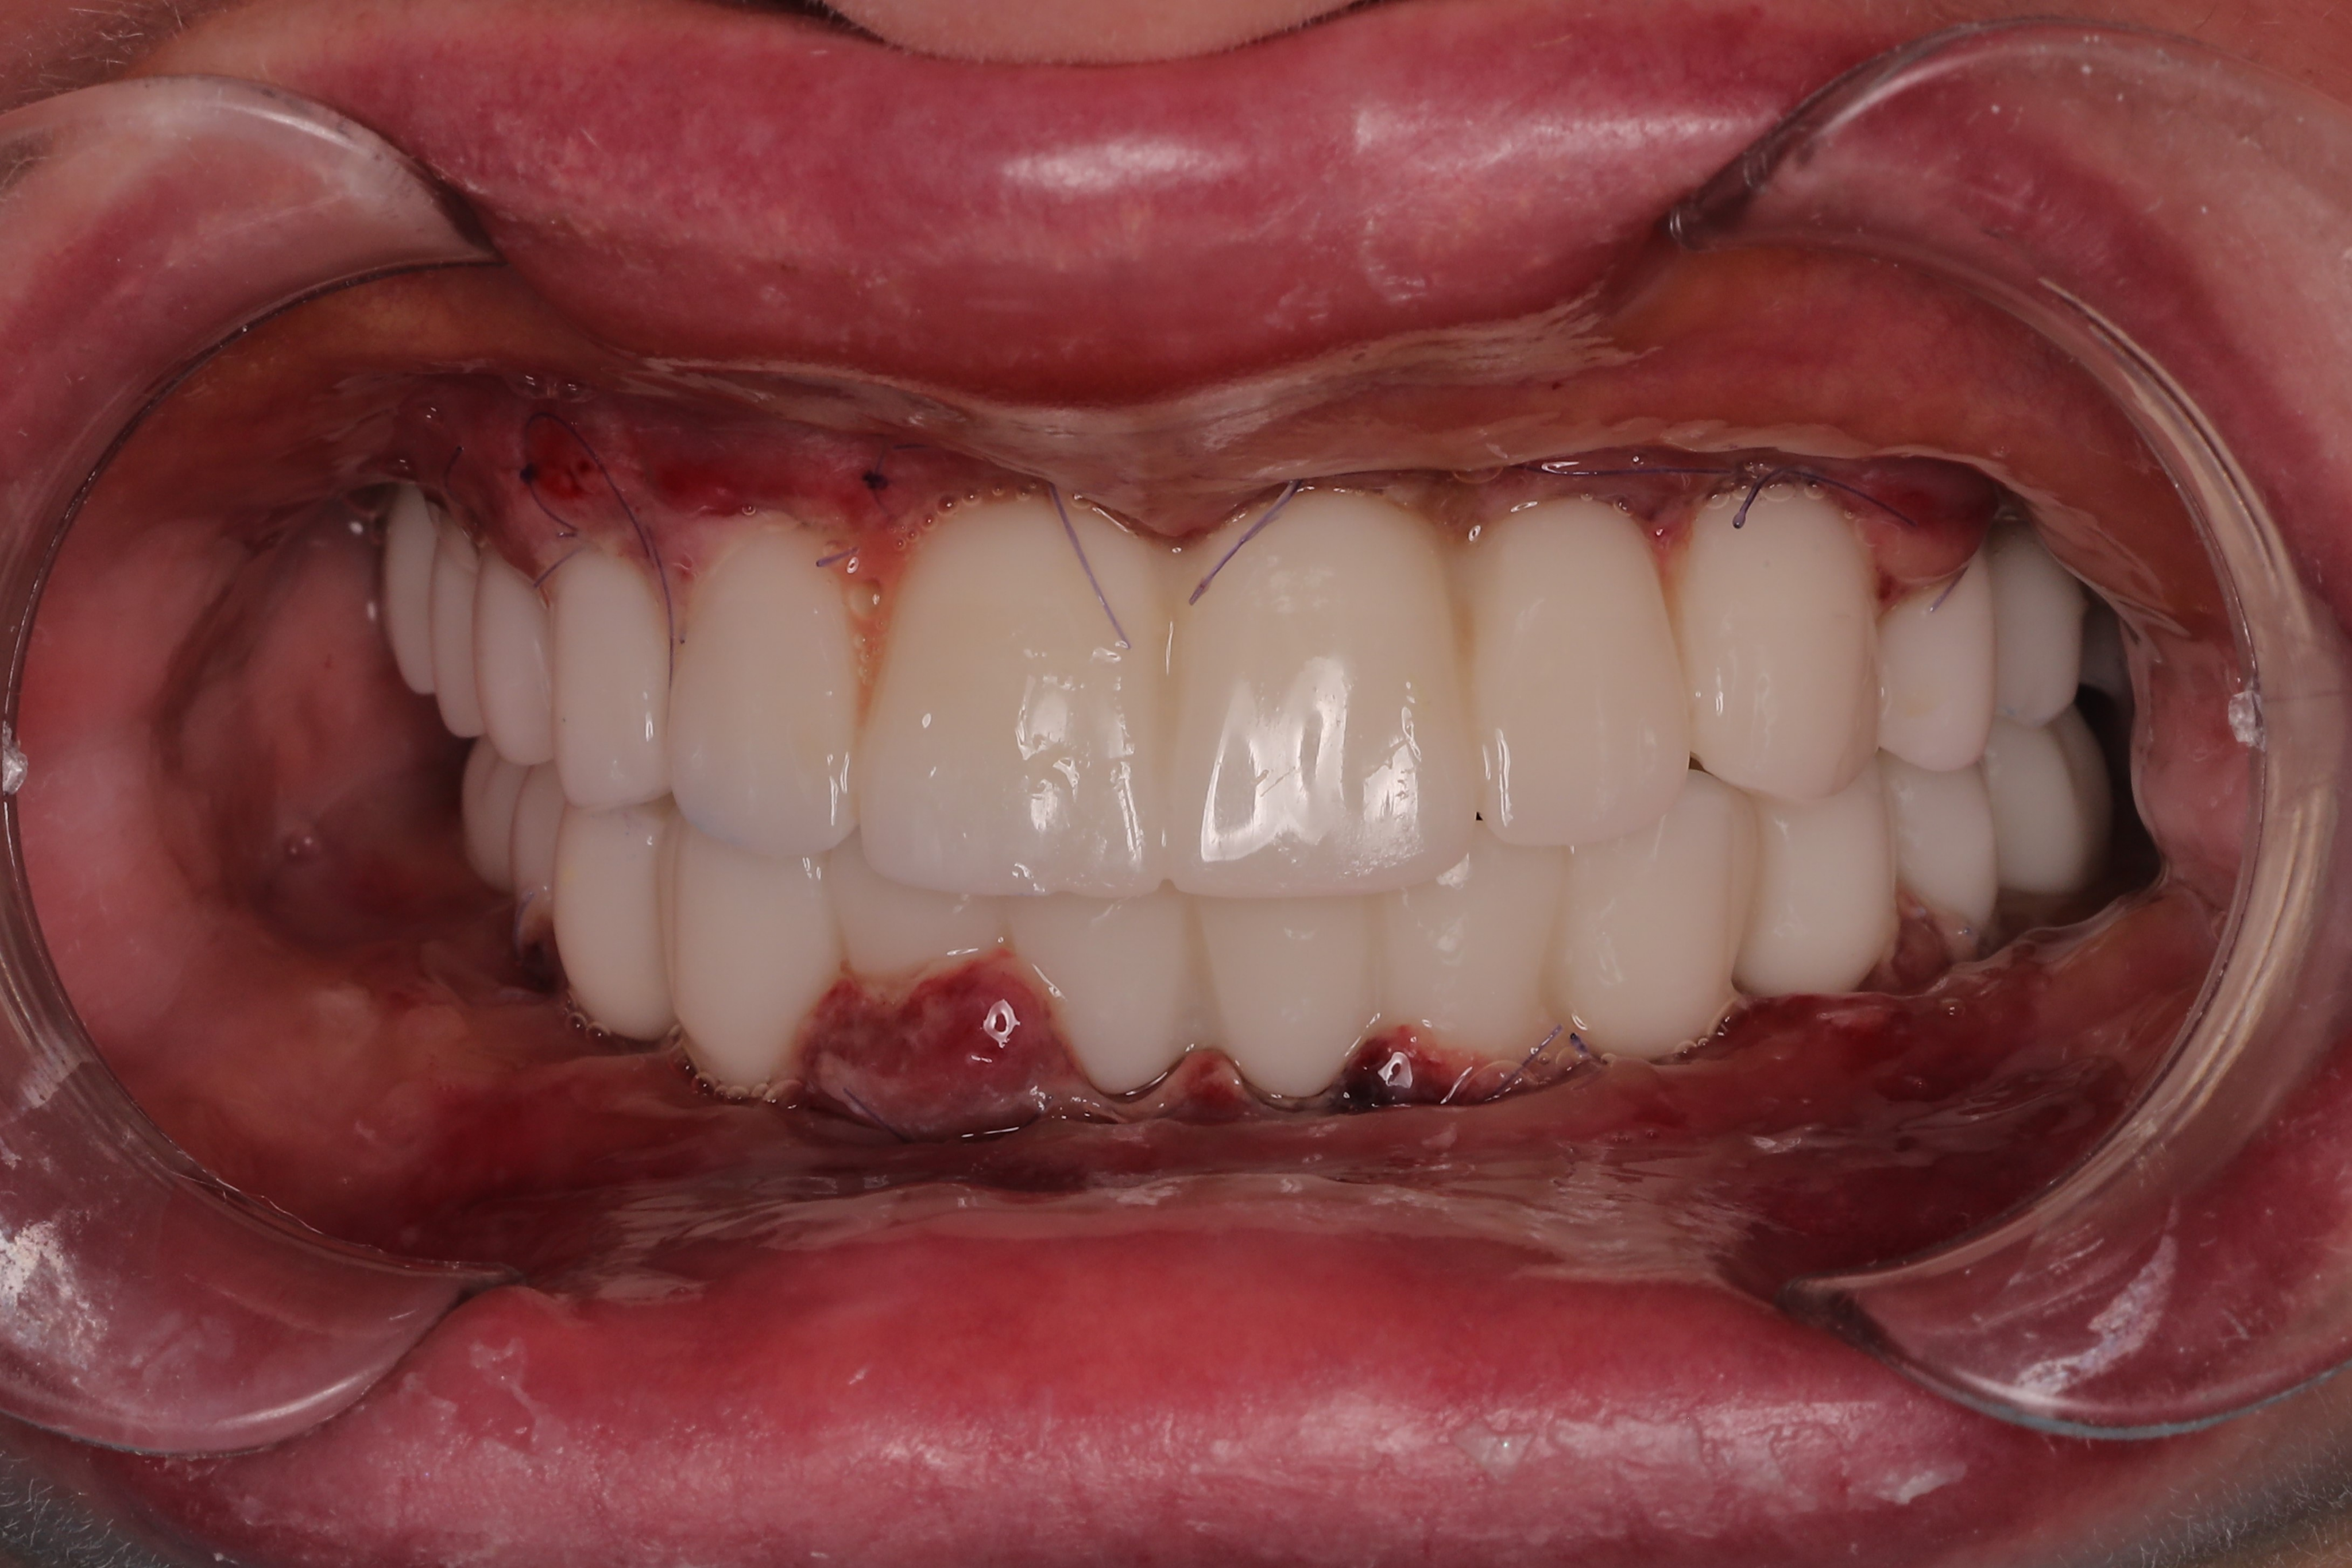

Based on the high-fidelity digital impressions, same-day resin provisional prostheses were fabricated and delivered immediately after surgery. The precision of the IPG scan ensured a successful same-day provisional bridge delivery and secure retention using Rosen screws without the need for titanium bases. Post-operative Orthopantomogram (OPTG) confirmed accurate seating and stable connections across all implants, with a 2 mm occlusal clearance maintained in the molar region to ensure functional safety during the initial healing phase.

At the six-month follow-up, the patient reported high satisfaction with the functional and aesthetic performance of the provisional restorations. Clinical examination following the removal of the provisionals revealed optimal soft tissue healing and well-preserved gingival architecture. Notably, the Root Shield sites at 13, 12, and 23 successfully maintained the buccal ridge contour, while radiographic evaluation (OPTG) confirmed complete osseointegration of all implants, including the pterygoid fixtures at sites 17 and 27.

The final restorative phase utilized a repeat IPG scan to ensure micron-level accuracy for the definitive frameworks. The maxilla was restored with a zirconia bridge on a titanium framework, while a metal-composite framework was selected for the mandible. The definitive prostheses achieved a perfect passive fit and optimal seating, successfully restoring both masticatory function and the patient’s natural aesthetic smile.